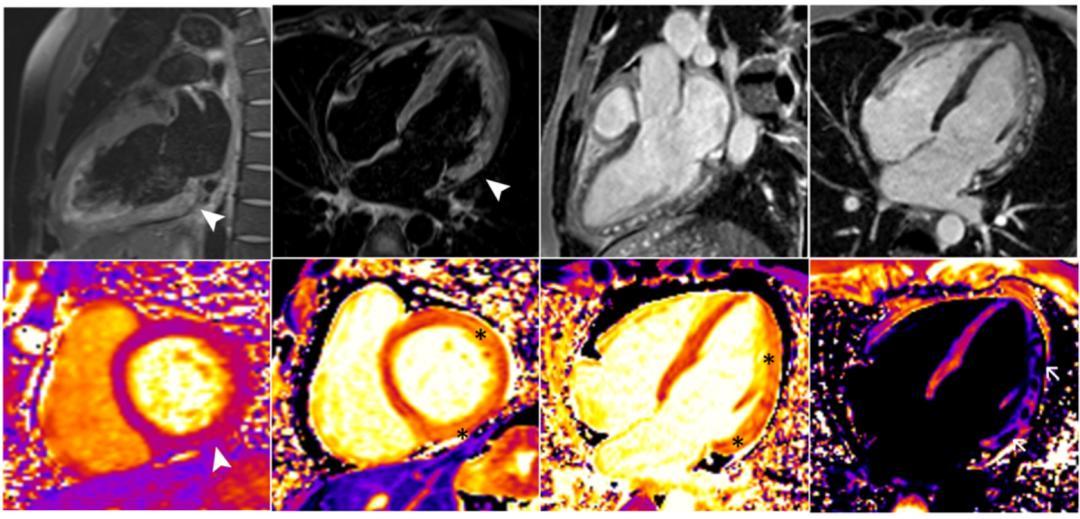

然而,猴痘的并发症风险不容忽视。据报道,这名31岁的男性患者在出现猴痘症状五天后到一家卫生所就诊,所出现的症状包括身体不适、肌痛、发烧以及面部、手部和生殖器的多处肿胀。通过对取自皮肤病灶的拭子样本进行PCR测试,确认为猴痘病毒感染阳性。三天后,这名患者回到急诊科,报告说胸闷并向左臂辐射。经初步常规检查,临床怀疑是急性心肌炎,随后被送入重症监护室。最初的心电图(ECG)显示窦性心律,伴有非特异性心室复极化异常,常规实验室检查显示C反应蛋白(CRP)、肌酸磷酸激酶(CPK)、高敏肌钙蛋白I和脑钠肽(BNP)的水平升高,所有这些指标都可以表明心脏遭受应激性损伤。对这名患者进行的心脏磁共振(CMR)研究结果与心肌炎症和急性心肌炎的诊断一致。

急性心肌炎的确诊金标准为心内膜活检(EMB),但是由于检查的危险性和特殊性,绝大部分医疗机构尚未开展此类技术。所以临床中我们首先要区分疑似心肌炎,在此之前,医生会完善以下相关检查和检验:肌酸激酶(CK)和肌钙蛋白(Troponin)评估心肌细胞的损伤情况;心电图(EKG)评估心脏有无心电学上的异常;超声心动图(UCG)主要评估心脏有无结构上的异常;心脏核磁共振(CMR)对评估心肌细胞的充血和水肿有很高的特异性。